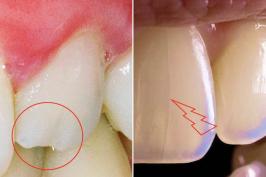

Bati o dente e trinquei o esmalte

03.01.2026 09h55

COLUNISTA